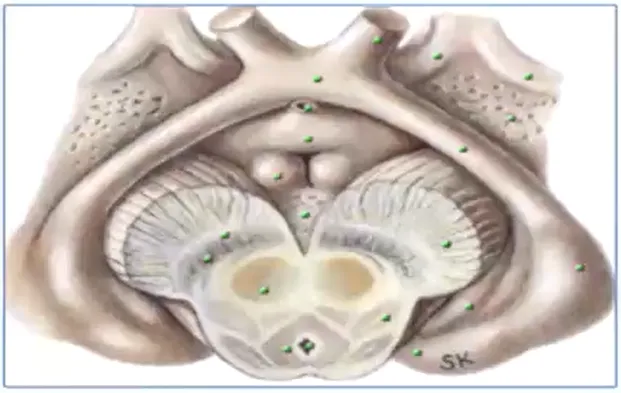

涉及的解剖结构包括:

视神经,视交叉,视束,视放射、丘脑底垂体轴、边缘系统、第三脑室、脑底动脉环。

图:绿色的点就是累及到视路-下丘脑的肿瘤生长的区域。一直从视路的后部视交叉,下丘脑、轴体以及大脑脚的后部。轴体是边缘系统的一部分,它连接着穹隆,如果损伤到这里那么会影响穹隆,会引起边缘系统症状。

图:仅有几千个这个神经纤维细胞在下丘脑和视路这个后部,我们都知道比如视下颌和视旁颌都是重要的神经内分泌的神经元。往往会如果影响到这些神经元的话,会产生非常严重的症状。